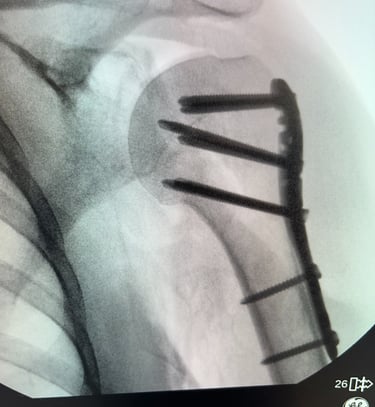

Mi occupo del trattamento traumatico sia in forma conservativa sia chirurgica. Tratto fratture, lussazioni, lesioni dei legamenti e dei tendini, con l’obiettivo di ripristinare la funzionalità articolare, ridurre il dolore e favorire un rapido ritorno alle attività quotidiane e sportive.